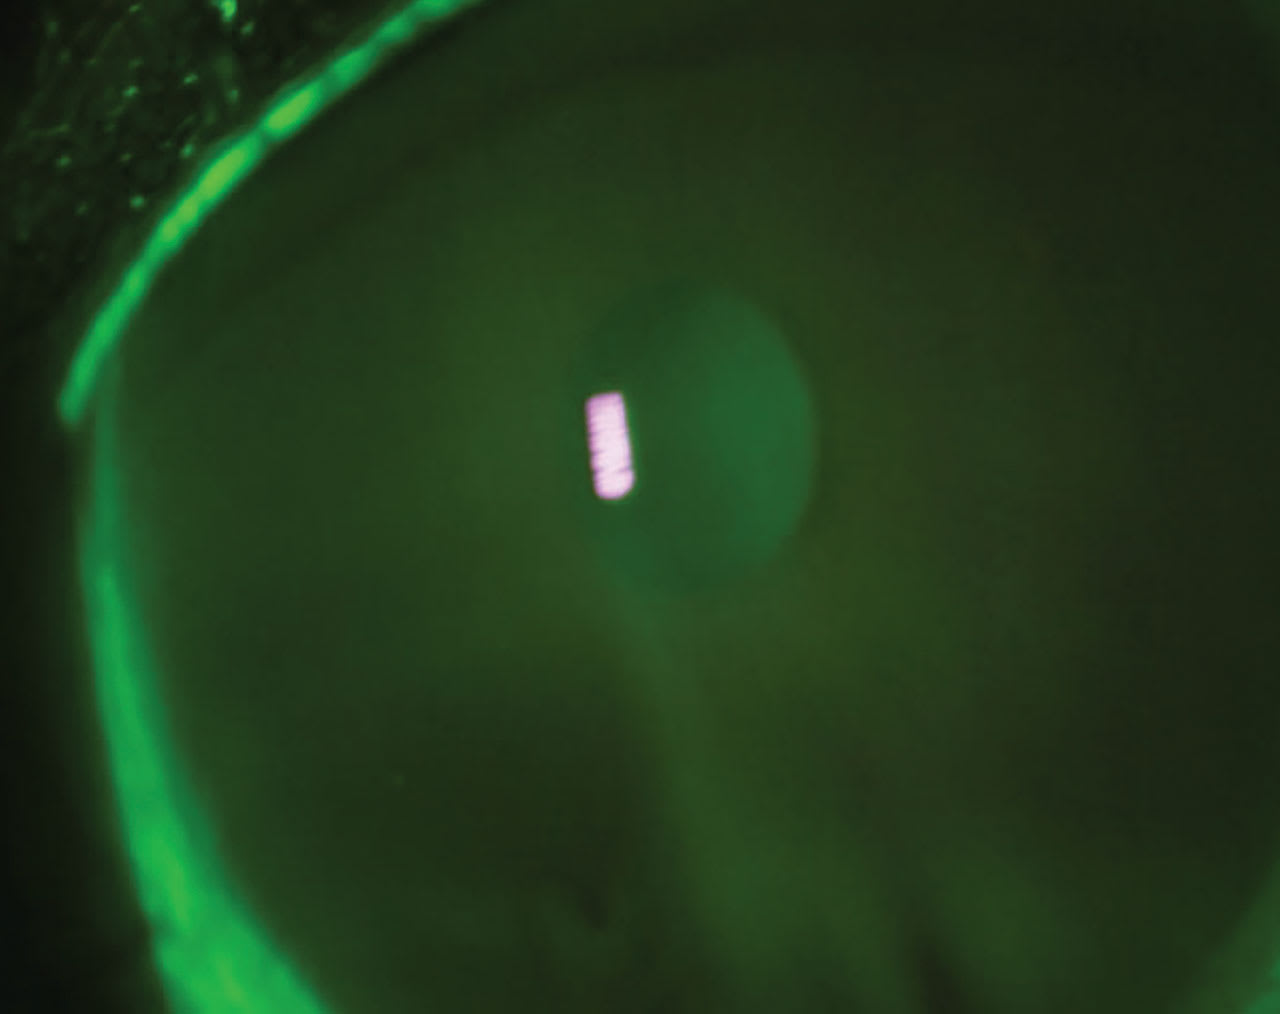

A 44-year-old male presented to the clinic with a chief complaint of severe pain, along with photophobia in his right eye for the past few days.

• Patient ocular history: ectasia secondary to laser-assisted in situ keratomileusis (LASIK) surgery for the past few years. The patient admitted to sleeping in his scleral contact lenses. Figure 3 displays the anterior segment image.

• Diagnosis:

1) corneal ulcer

2) ectasia

• Treatment: Approaching a compromised cornea with underlining conditions such as keratoconus or post-refractive complications must be aggressive but guarded. In this case, it was a cryopreservative slim-profile amniotic membrane, besifloxacin q.i.d. to the affected eye, and artificial tears every 30 minutes. Figure 4 shows the eye with an AMCL over the compromised cornea. Figure 5 shows an image three days after removal.